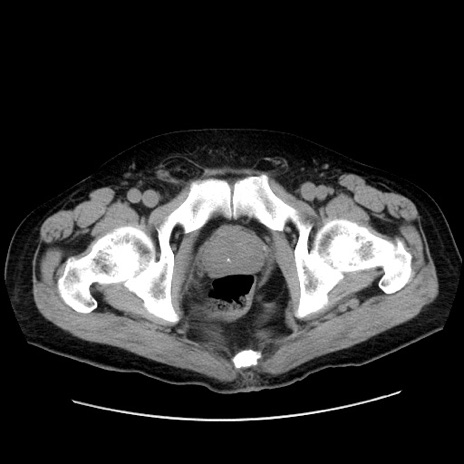

症例30(横断像)

【症例】80歳代男性

【主訴】臍周囲痛

【現病歴】約6時間前から臍下部痛が出現。次第に腹部膨隆・背部痛も生じてきたため来院。背部痛の場所は変化しない。

【身体所見】意識清明、BT 36.3℃、BP  131/87mmHg、P 87bpm、SpO2 100%(RA)、臍周囲自発痛・圧痛あり、反跳痛なし、自発痛部位に一致して板状硬あり、腹部膨隆、腸雑音減弱、CVA tenderness両側陰性。